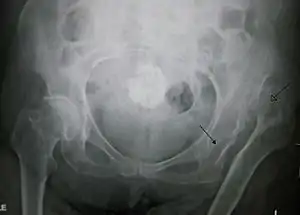

![]() | |

| Congenital dislocation of the left hip in an elderly person. Closed arrow marks the acetabulum, open arrow the femoral head. | |